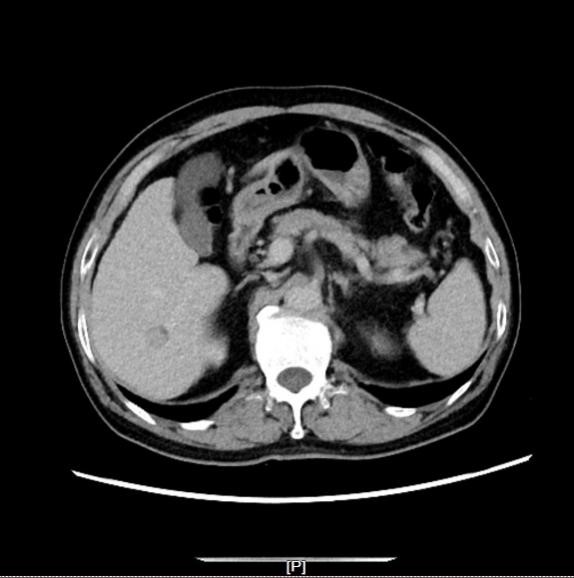

(体检CT见肝S2段见类圆形低密度影)